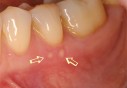

• Aphtes Conseils pour les éviter

Tout le monde en a eu, mais personne ne sait très bien pourquoi. Franchement banal, souvent bénin, l’aphte est à coup sûr douloureux. La bonne conduite pour les éviter.

• A-t-il de graves conséquences ?

On sait tous ce que sont les aphtes, enfin on croit le savoir. Pourtant, on les confond souvent avec d’autres lésions de la bouche ou même des infections oropharyngées… Chassons les idées reçues !